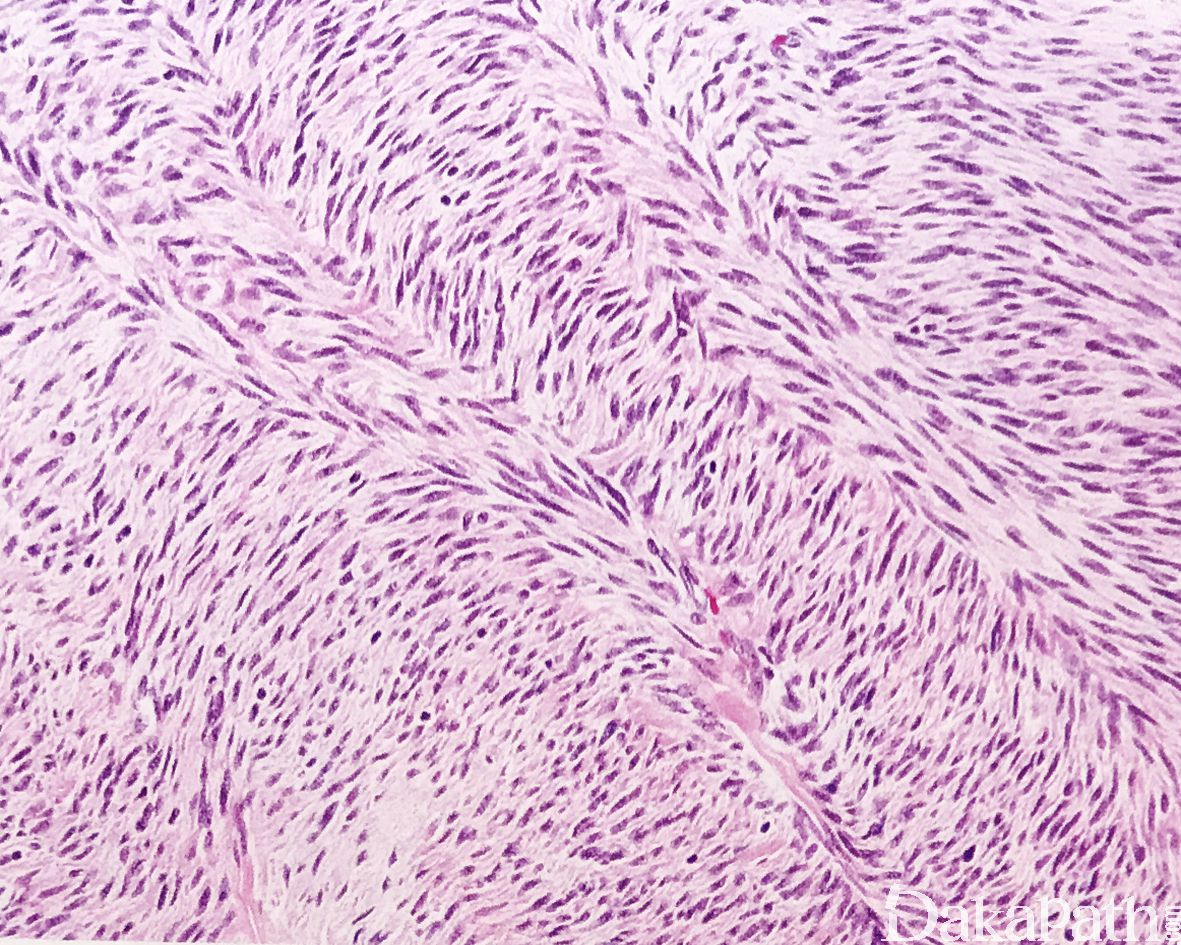

镜下见由长梭形细胞呈束状排列,也可呈席纹状、交织的束状或漩涡状排列,或呈波浪状排列;

细胞质强嗜酸性,原纤维状,核呈长卵圆形,两端稍钝,多数病例可见散在的横纹肌母细胞;

瘤细胞的异型性不明显,可见少数核分裂像;